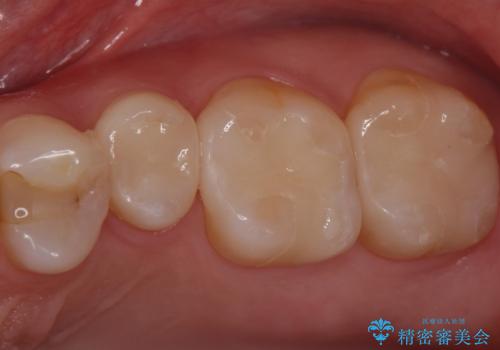

奥歯が欠けた セラミックインレーでの修復後、ナイトガード装着

![[e-maxインレー] 矯正治療前の虫歯治療の症例 治療前](https://seimitsushinbi.jp/wp/wp-content/uploads/2023/08/IMG_1022-2-500x350.jpg?v=1691812242)